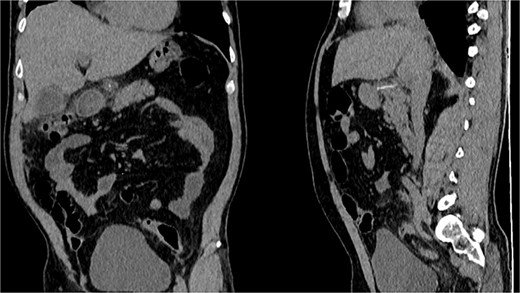

CT, the location of the fishbone in the lesser sac embedded in the pancreas.